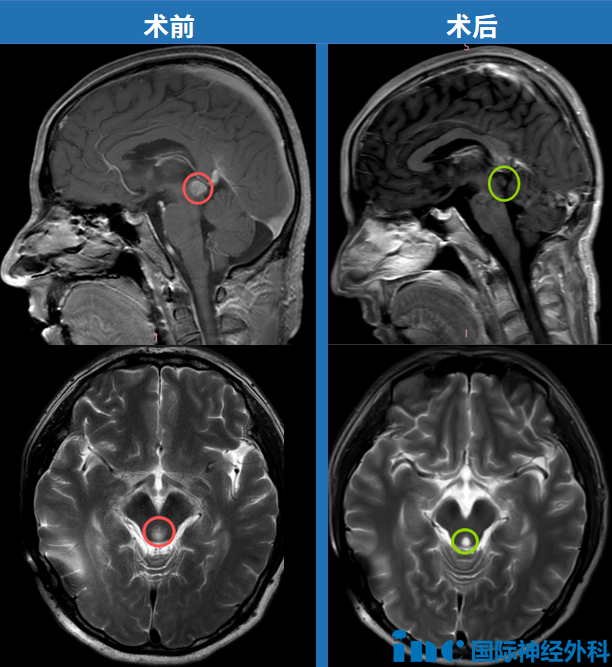

巴教授最新随访截图

令家人感到高兴的是,他术后的两次随访检查均显示肿瘤得到完全切除,无残留病灶,脑干、丘脑等重要结构均保持完整,他也无需再进行额外的放疗。